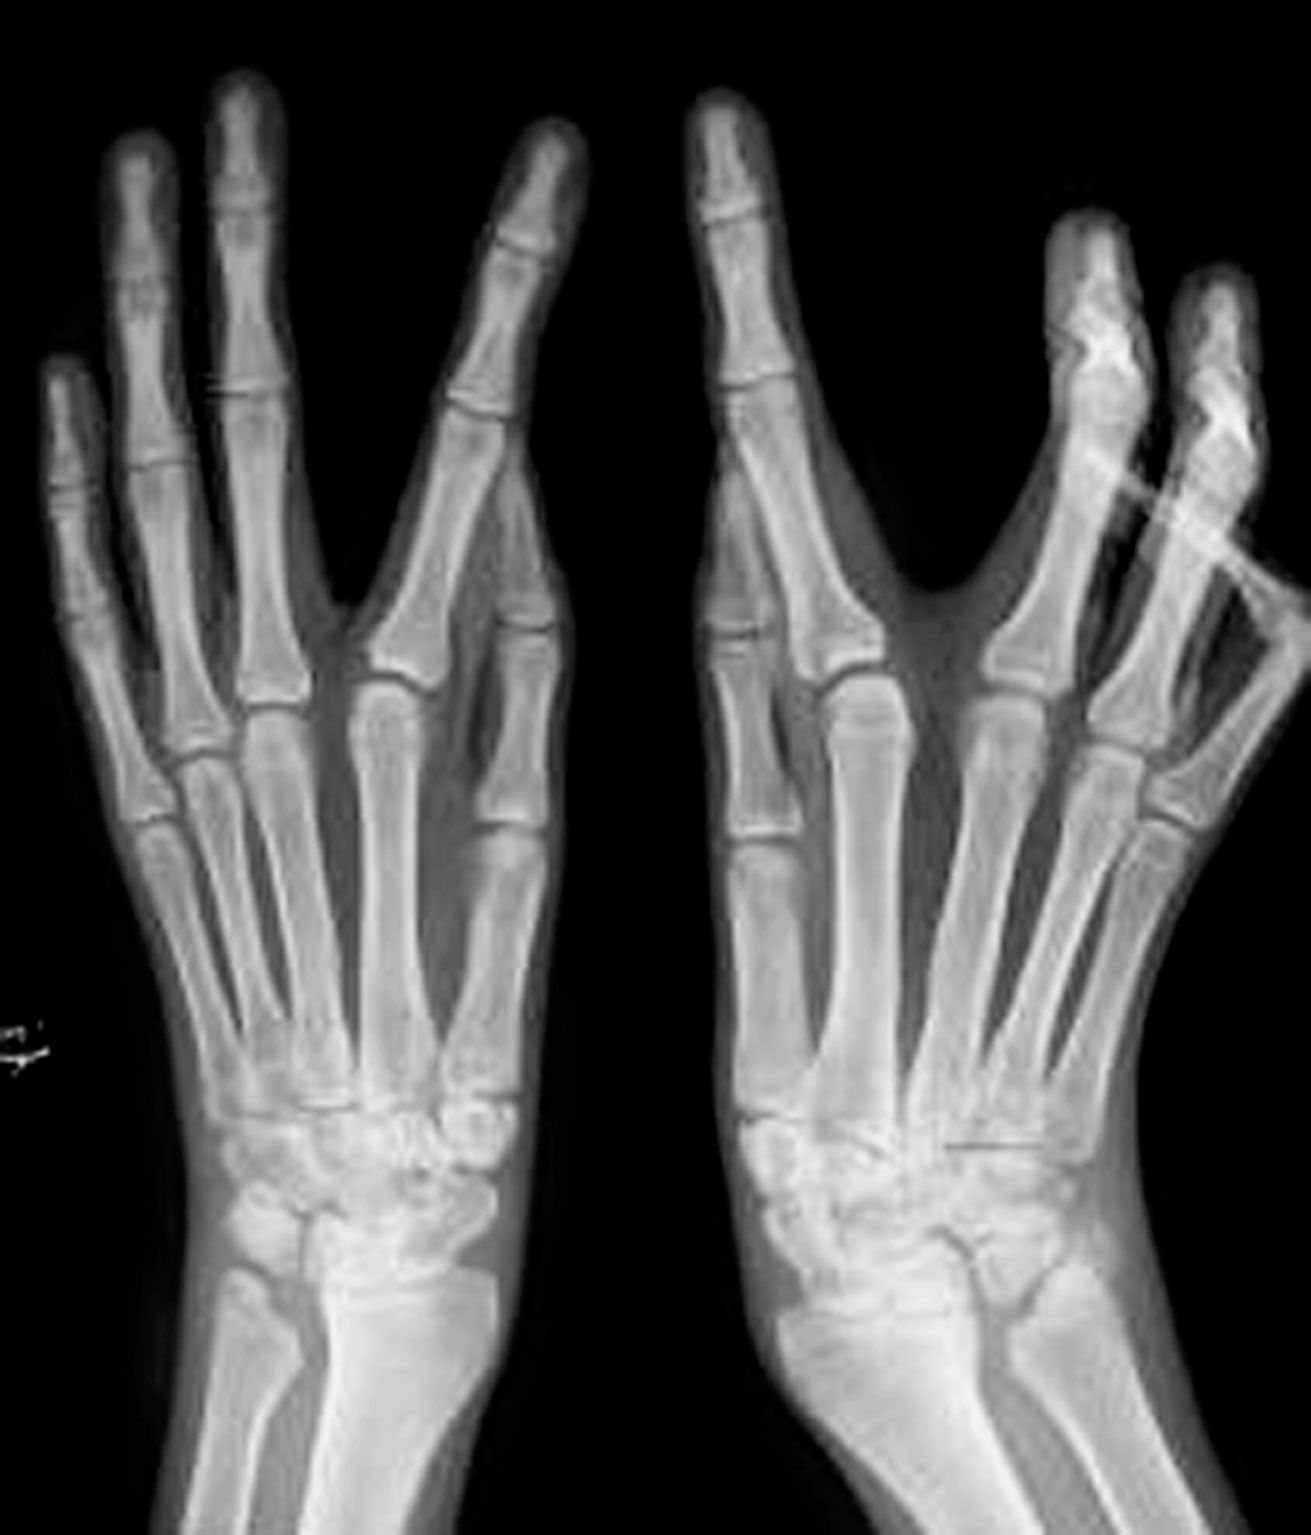

图1-2-40 孪生手畸形病例

A.右手镜影手(患手共7 个手指);B.X 线片显示双尺骨畸形

镜影手患儿多同时表现为双尺骨畸形(图1-2-40)。